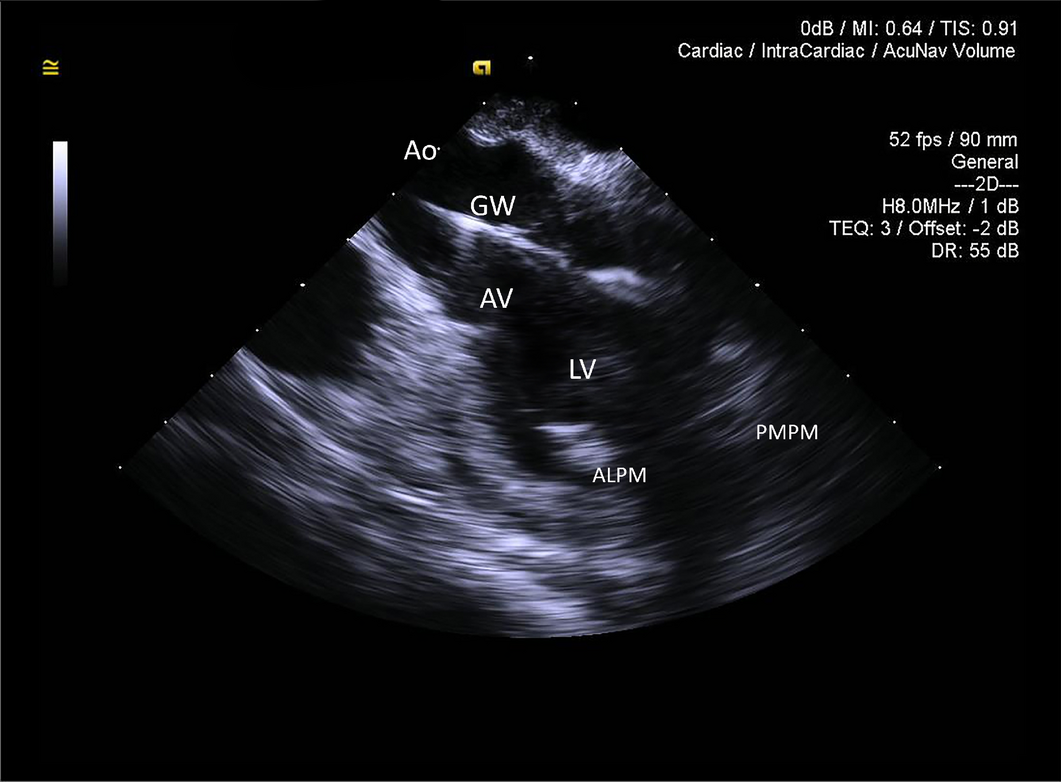

Figure 7

2D ICE long-axis image of the ascending aorta (Ao), aortic valve (AV) and left ventricle (LV). Both papillary muscles are imaged (ALPM anterolateral papillary muscle, PMPM posteromedial papillary muscle). The Impella guidewire (GW) is seen traversing aortic valve and entering left ventricular cavity. The tip of the guidewire is off-plane, creating false impression that the guidewire is terminating in mid-LV cavity.